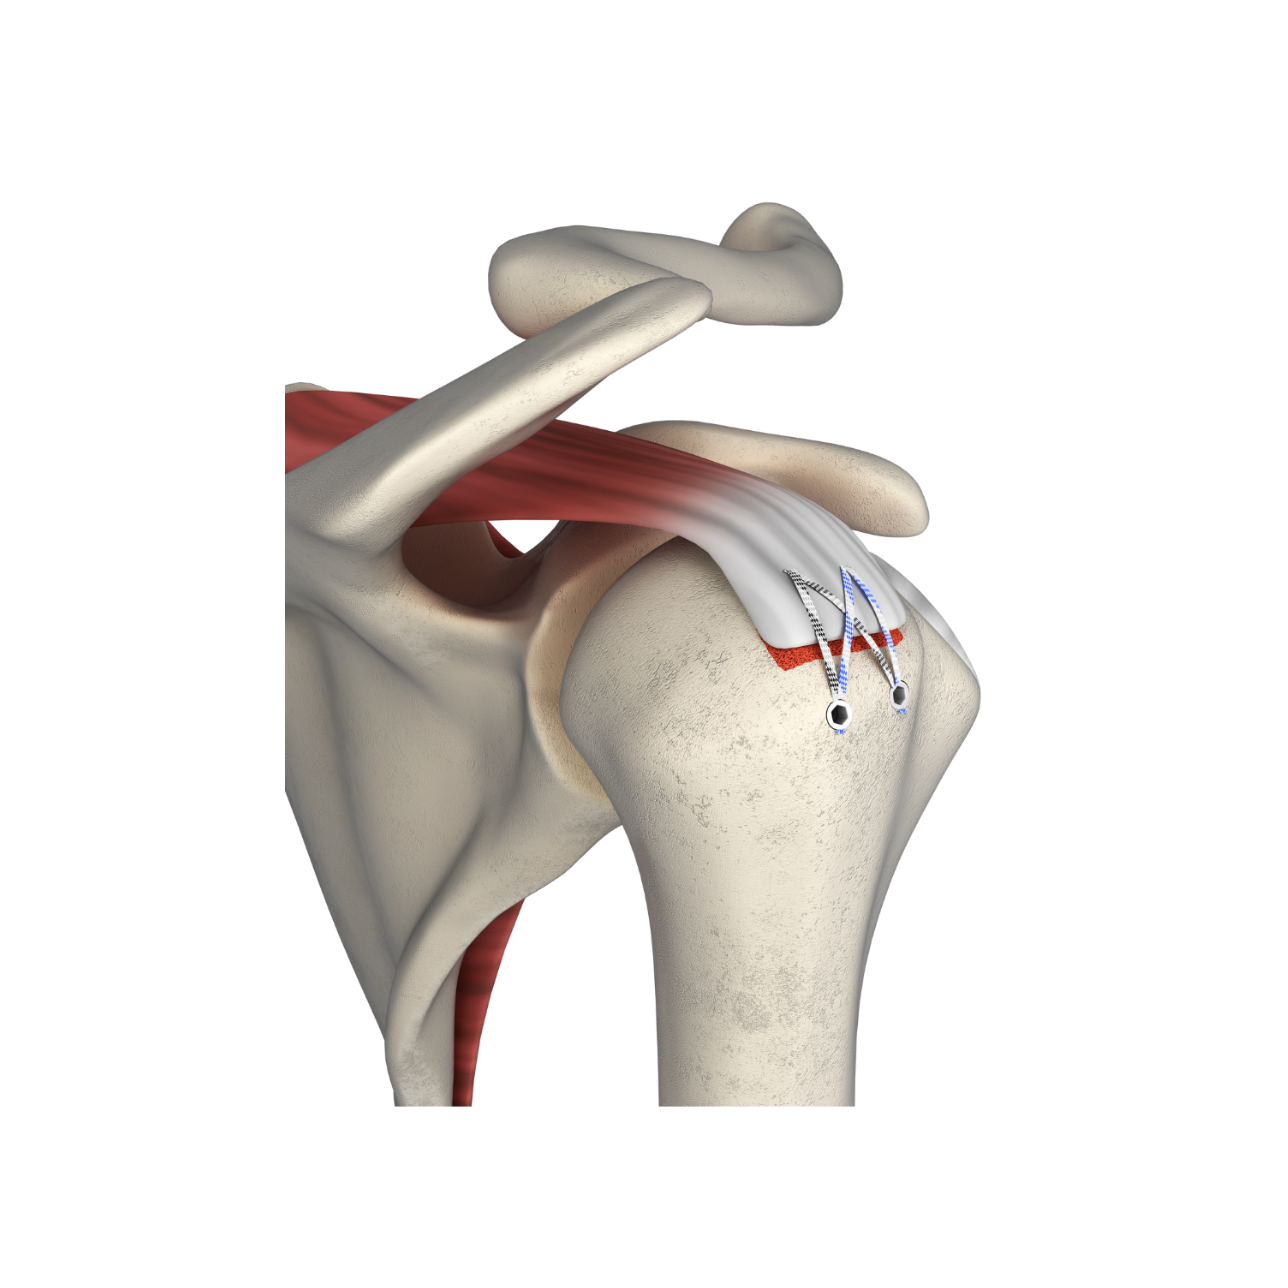

fThis technique features knotless fixation of the rotator cuff using 2 pcs of PEEK Suture Anchors (for medial row) with Fiber Tape and 2 pcs of PEEK Knotless anchors (for lateral row). Knotless PEEK Suture Anchor is available in diameter of 4.75 and 5.5mm with 1 pc of locking Fiber Tape and 1 pc of Fiber Wire. The anchor is inserted in the medial row of the rotator cuff. These Fiber Tapes are passed through the cuff tissue and then loaded into Knotless PEEK Suture Anchor and it is fixed on the lateral row using knotless anchor. The technique eliminates the need for multiple suturing passes, reducing post-operative pain and recovery time. It also increases the structural integrity of the repair, ensuring a lasting and secure fix. It is a predural time saving than the regular knot tying repairs.